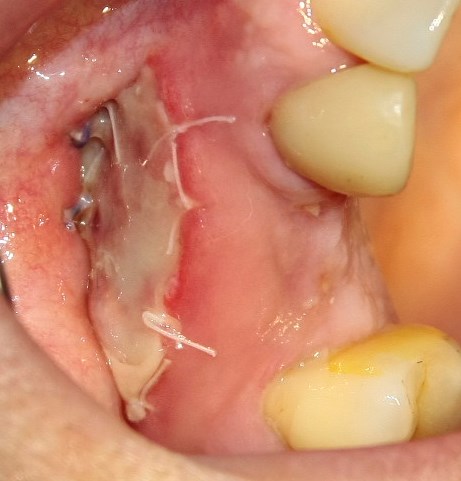

Опыт применения коллагеновой матрицы Mucograft в клинической практике.